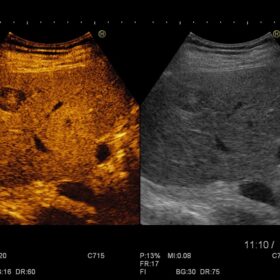

Radiology 2D, Color, PW and Elasto mode

- Dynamic Contrast Harmonic Imaging (dCHI)